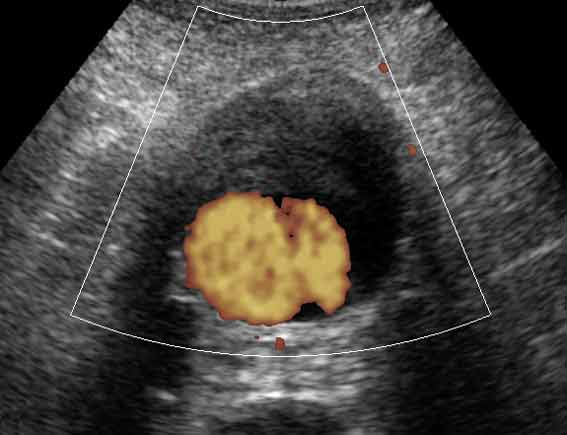

Александр Маркович, на УЗИ в поперечном сканировании ЭТО может выглядеть примерно так:

Ну, это ж совсем другое дело!!!KapustinSV писал(а): ...на УЗИ в поперечном сканировании ЭТО может выглядеть примерно так:

Ну да.А.М.Шифрин писал(а):Ну, это ж совсем другое дело!!!KapustinSV писал(а): ...на УЗИ в поперечном сканировании ЭТО может выглядеть примерно так: